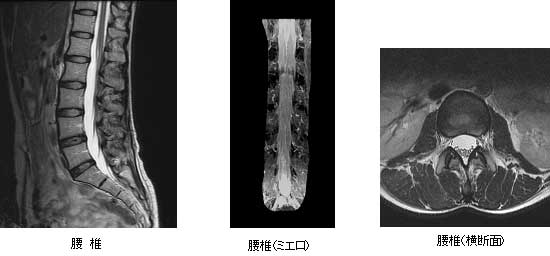

整形外科領域

脊椎領域では、椎間板ヘルニアや脊柱管狭窄症における神経圧迫の程度が鮮明に描出できます。

また、造影剤を使用せずに脊髄造影像と同様な画像を構成することが可能です。

その他の整形外科領域において、一般的にX線にて評価の困難とされる筋肉や靭帯、軟骨などの評価にも有用で四肢や股関節などの関節疾患、腫瘍性病変の検索、評価と使い方は多種多様です。